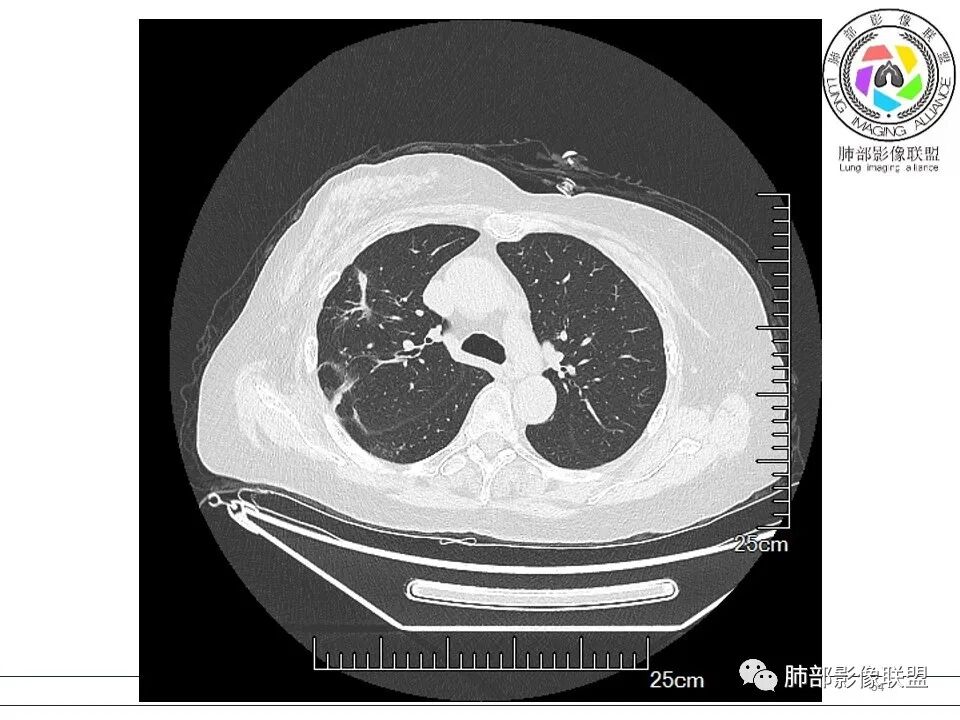

谢加平: 右肺上叶外周,近胸膜下结节病灶,侧向融合,边缘清,见平直边,与胸膜平行分布,支气管进入略扩张,周围见多发长索条影,方向肉芽肿性炎症,建议隐球菌荚膜抗原检查,肿瘤不支持,经皮肺穿刺病理检查!

宇宙: 右肺上叶胸膜下结节,多结节融合,长轴平行胸膜,边缘模糊,周围长索条,胸膜牵拉,近端支气管充气扩张,考虑隐球菌,鉴别OP

衡妈: 老年女性,右肺上叶沿胸膜下不规则实性病灶,长轴平行于胸膜,有结节融合感,边缘部分彭隆部分平直,周围可见数条纤维灶影,病灶内可见充气支气管征未达远端,首诊考虑慢性炎性肉芽肿,隐球菌?机化性肺炎?建议增强扫描及ct下穿刺活检。

张延军: 病变与胸膜平行,近端见气管进入,口服激素治疗史 考虑隐球菌感染 伴OP样改变

瑞欣 (刑瑞欣): 晨读,老年女性,右肺上叶不规则高密度影,可见胸膜牵拉,边缘光滑平直,与胸膜平行,周围条状影,可见支气管充气征,有风湿病史,考虑机化性炎症,鉴别隐球菌,腺癌

南边: 这个病例大方向没问题,炎性。目前大家都是考虑:隐球菌病、OP,其实这两个结论有重叠,而且这个病例很值得讨论,可惜,估计没有证实。影像特点:病灶长轴与胸膜平行,侧向融合特点明显,符合隐球菌病,问题是目前的状态,边缘收缩明显

内部支气管扩张,周围少量GGO,而且病灶离开了胸膜,附近长索条影,支持机化的改变